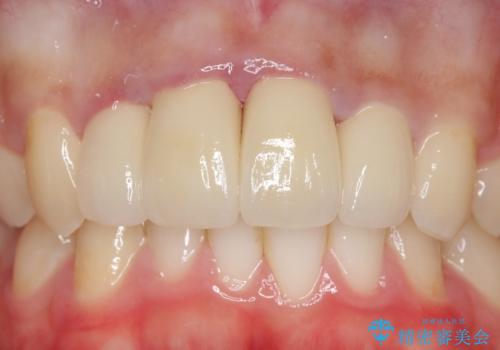

- 上顎前歯の歯並びが気になるが仕事が忙しく矯正治療は難しいため、セラミック矯正で綺麗にしたいといらっしゃった方の症例です。

左右の1番目の歯は傾きが大きいため、セラミッククラウンにするにあたり神経治療を行うことを御了承頂いた上で、前歯4本をオールセラミッククラウン(スペシャル)により補綴しました。

前歯の補綴ではオールセラミッククラウンを希望される患者様が多いですが、オールセラミッククラウンの中でも、エコノミー、スタンダード、スペシャル、エクセレントとランクがあります。

その中でも特に審美性が高いのがスペシャル、エクセレントです。スペシャル、エクセレントは口腔内写真をもとに熟練の技工士が、患者様の口腔内に合わせたオーダーメイドのクラウンを製作致します。